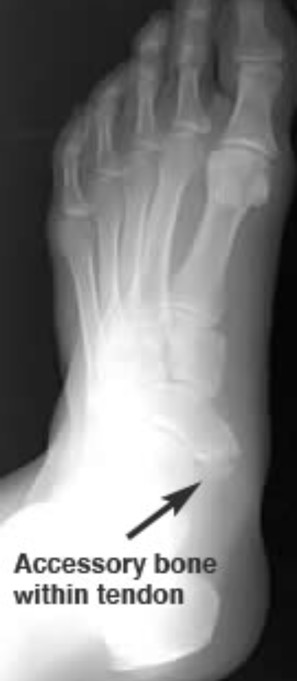

Extra Bones

These accessory bones are usually weaker than their normal anatomic counterparts, and can be injured more easily, but without them your tendon would have not where to attach itself to. If this were to case, you would not have function of that joint and or limb.